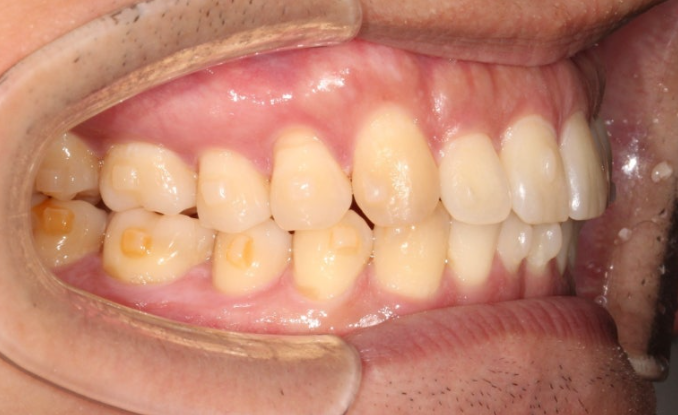

중심선은 처음에 비해 많이 맞아졌고 여전히 약간의 불일치가 남아있습니다.

아래 작은어금니의 완벽한 회전을 위해서 고무를 걸 부가장치를 붙인채 치료를 진행했습니다.

안으로 쓰러져 있던 큰어금니도 잘 세워졌고 가위교합도 해소가 되었습니다.

또 고무줄의 힘으로 아래 작은어금니 회정는 1차세트에서 대부분 개선이 됩니다.